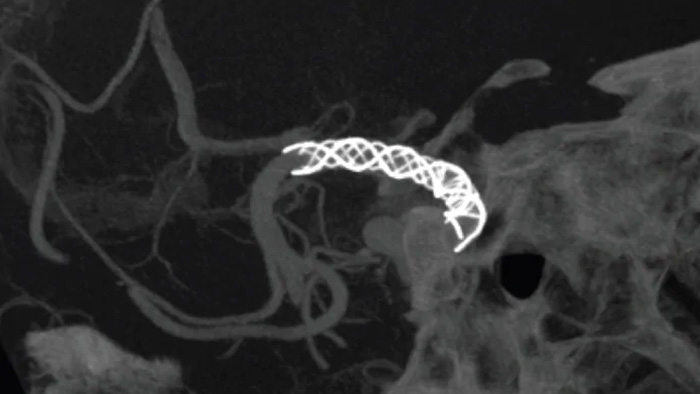

SmartCT Vaso verbessert die Darstellung endovaskulärer Stents, Flow Diverter und anderer Instrumente sowie der Gefäßmorphologie bis auf Perforatorebene. Diese Erfassungstechnik basiert auf einem Cone-Beam-CT-Scan in Kombination mit einer intraarteriellen Kontrastmittelinjektion. Sie wird zunehmend zur Nachkontrolle von mit Flow-Diverter-Stents behandelten Aneurysmen verwendet, um die Positionierung des Implantats zu überprüfen.